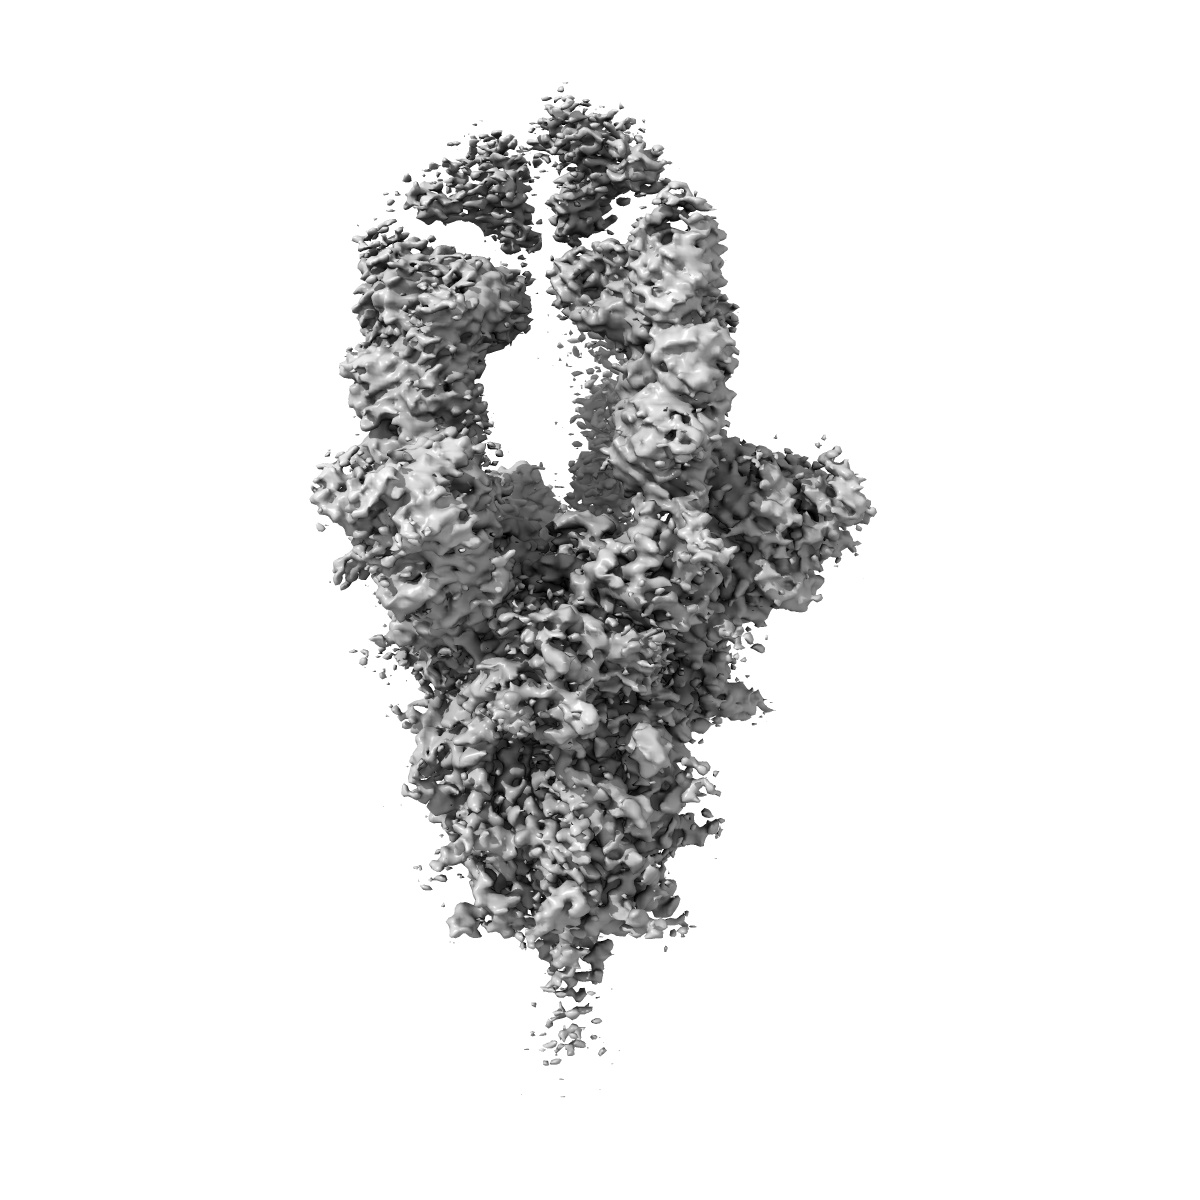

S728-1157 IgG in complex with SARS-CoV-2-6P-Mut7 Spike protein (global refinement)

Single-particle3.3 Å

Sample: S728-1157 IgG in complex with SARS-CoV-2-6P-Mut7 S protein